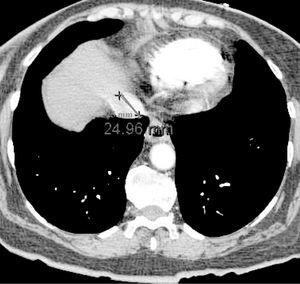

Paciente de 73 años de edad que ingresa en la Unidad de Cuidados Críticos por síncope e hipotensión arterial refractaria a la administración de fluidos intravenosos. En la tomografía axial computarizada (TAC) torácica helicoidal realizada, con protocolo de tromboembolismo pulmonar, se observan signos de embolismo pulmonar extenso con afectación de arterias pulmonares principales y lobares de ambos hemitórax. Igualmente se aprecian signos de sobrecarga ventricular derecha e hipertensión pulmonar. En la figura 1 se observa la dilatación del ventrículo derecho, con índice de diámetro de ventrículo derecho/diámetro de ventrículo izquierdo mayor de 1,5; la flecha indica el abombamiento del septo inter-auricular. En la figura 2 se aprecia, además, reflujo de contraste intravenoso a la vena cava inferior, que se encuentra dilatada. Por tanto, los hallazgos tomográficos podrían servir para valorar de forma indirecta la sobrecarga aguda del ventrículo derecho, secundaria a un tromboembolismo pulmonar.

Figura 2.